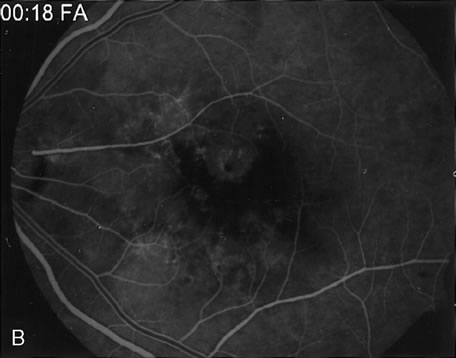

FA is generally not necessary to make the diagnosis of cystoid macular edema (CME). A history of recent cataract surgery, diabetes, uveitis, or other predisposing conditions is usually obtained. Clinically, the patient presents with retinal thickening, often with clinically evident cystic changes. FA reveals a characteristic petaloid collection of fluorescein that confirms the diagnosis, which has been shown histologically to reflect accumulation of fluid in the extravascular component of the outer plexiform layer.239 When FA demonstrates leakage from the optic nerve, this suggests an inflammatory etiology for the CME (Fig. 36). Although this sign is reliably present in CME associated with cataract surgery, penetrating keratoplasty, or posterior uveitis, it is not characteristically present in diabetics or in idiopathic CME. FA can also demonstrate dilated macular capillaries as a cause of CME in diabetes (Fig. 37). Different conditions that may cause CME include Irvine-Gass syndrome, previous penetrating keratoplasty, any inflammatory condition that involves the posterior segment, peripheral rhegmatogenous retinal detachment, peripheral cryotherapy, malignant melanoma, topical epinephrine, tapetoretinal degenerations, juxtafoveal telangiectasia, occult central retinal vein occlusion, nicotinic acid maculopathy, and idiopathic CME.

Fig. 36. Cystoid macular edema (CME). This patient had bilateral vitritis and CME. A. Early-phase photograph of the right eye reveals telangiectasia of the perifoveal retinal capillaries with some early leakage visible temporally. B. Mid-phase photograph of the left eye reveals more intense fluorescence leakage. C. Late-phase photograph of the left eye demonstrates cystic accumulation of fluorescein in a classic “petaloid” configuration. The late-phase staining of the optic nerve head in this fluorescein angiogram suggests an inflammatory cause of the CME.